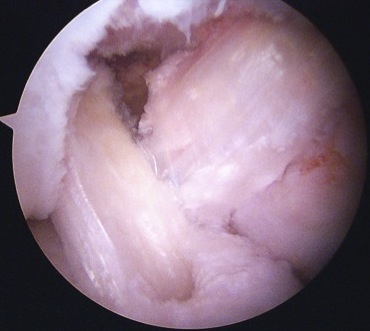

Need adequate visualisation of the PCL facet

- down at least 1 - 2 cm below articular surface

- combination of shaver and electrocautery

- usually need to release some of the capsular insertion onto posterior tibia

PCL facet 1PCL tibial tunnel

PCL tibial facet                                                           Tibial tunnel beath pin